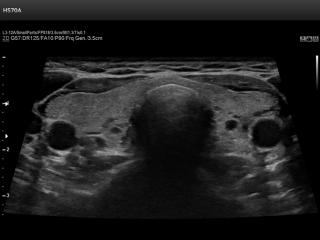

В разделе "Поверхностно расположенные органы" атласа наиболее полно представлены результаты ультразвуковых исследований щитовидной железы. Здесь можно посмотреть эхограммы: щитовидная железа в норме, гипертиреоз, киста, узел и др.